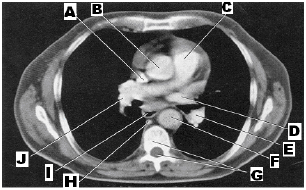

Entre as alternativas abaixo, qual apresenta uma estrutura que

não

está identificada na imagem, considerando que o corte axial ilustrado foi feito 1 cm abaixo da Carina?

A

aorta ascendente

B

veia cava inferior

C

veia cava superior

D

artéria pulmonar principal